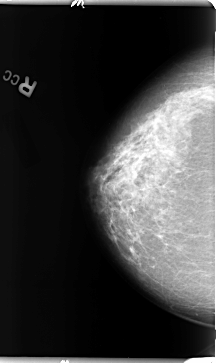

B_3096_1.RIGHT_CC

LEFT_CC LINES 4736 PIXELS_PER_LINE 2624 BITS_PER_PIXEL 12 RESOLUTION 50 OVERLAY

FILE: B_3096_1.LEFT_CC.OVERLAY

TOTAL_ABNORMALITIES 1

ABNORMALITY 1

LESION_TYPE MASS SHAPE IRREGULAR MARGINS OBSCURED

ASSESSMENT 3

SUBTLETY 2

PATHOLOGY BENIGN

TOTAL_OUTLINES 1

BOUNDARY